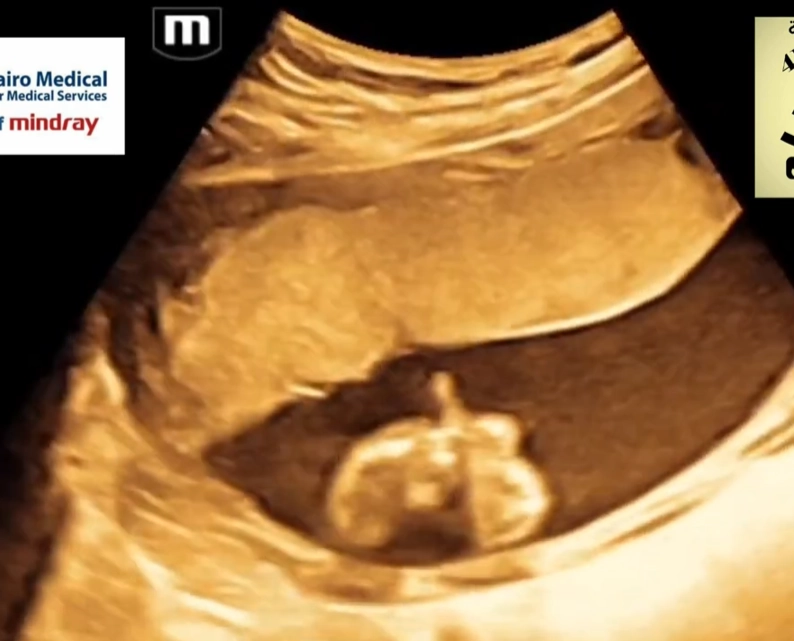

Cứng đa khớp bẩm sinh (Arthrogryposis Multiplex Congenita - AMC)/Chuỗi biến dạng do thai nhi bất động/giảm động (Fetal Akinesia/Hypokinesia Deformation Sequence - FA(H)DS)